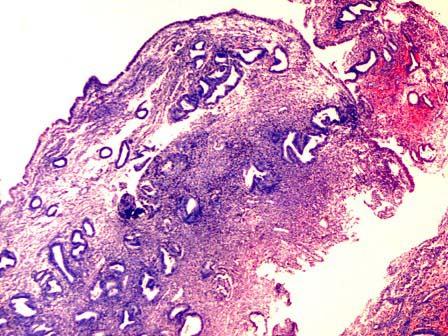

问题 女性,46岁,因月经量不规律检查,B超发现子宫内一新生物。行子宫切除,大体见子宫底一蒂状物突出(如图)。显微镜下由腺体和纤维化间质组成(如图),易见厚壁血管。诊断为 ( )

选项 A.慢性子宫内膜炎 B.子宫内膜息肉 C.子宫平滑肌瘤 D.子宫内膜腺肌瘤 E.子宫内膜结核

答案 B